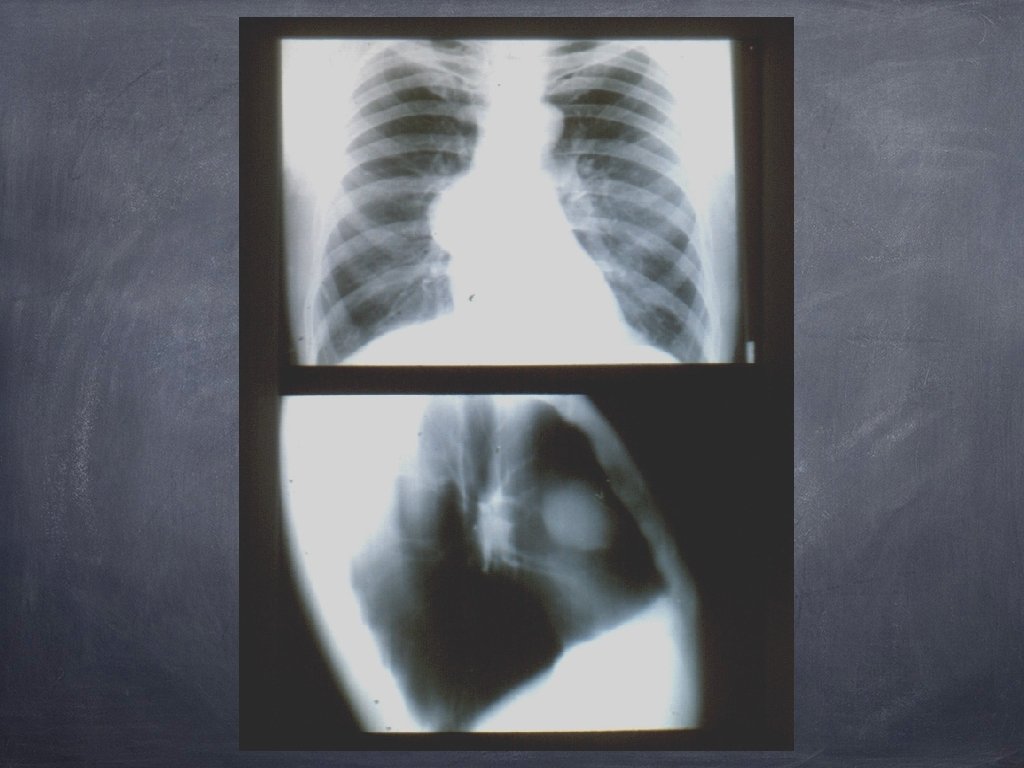

Semnul siluetei